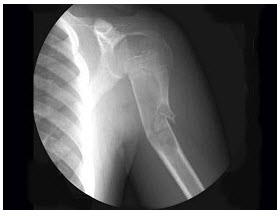

5、单项选择题

男,28岁,右肱骨上段肿痛1个月,疼痛以夜间明显,摄片如图所示,提示骨肉瘤最为主要的征象是()

A.溶骨性破坏

B.骨膜增生

C.肿瘤骨形成

D.软组织肿块影

E.Codman三角